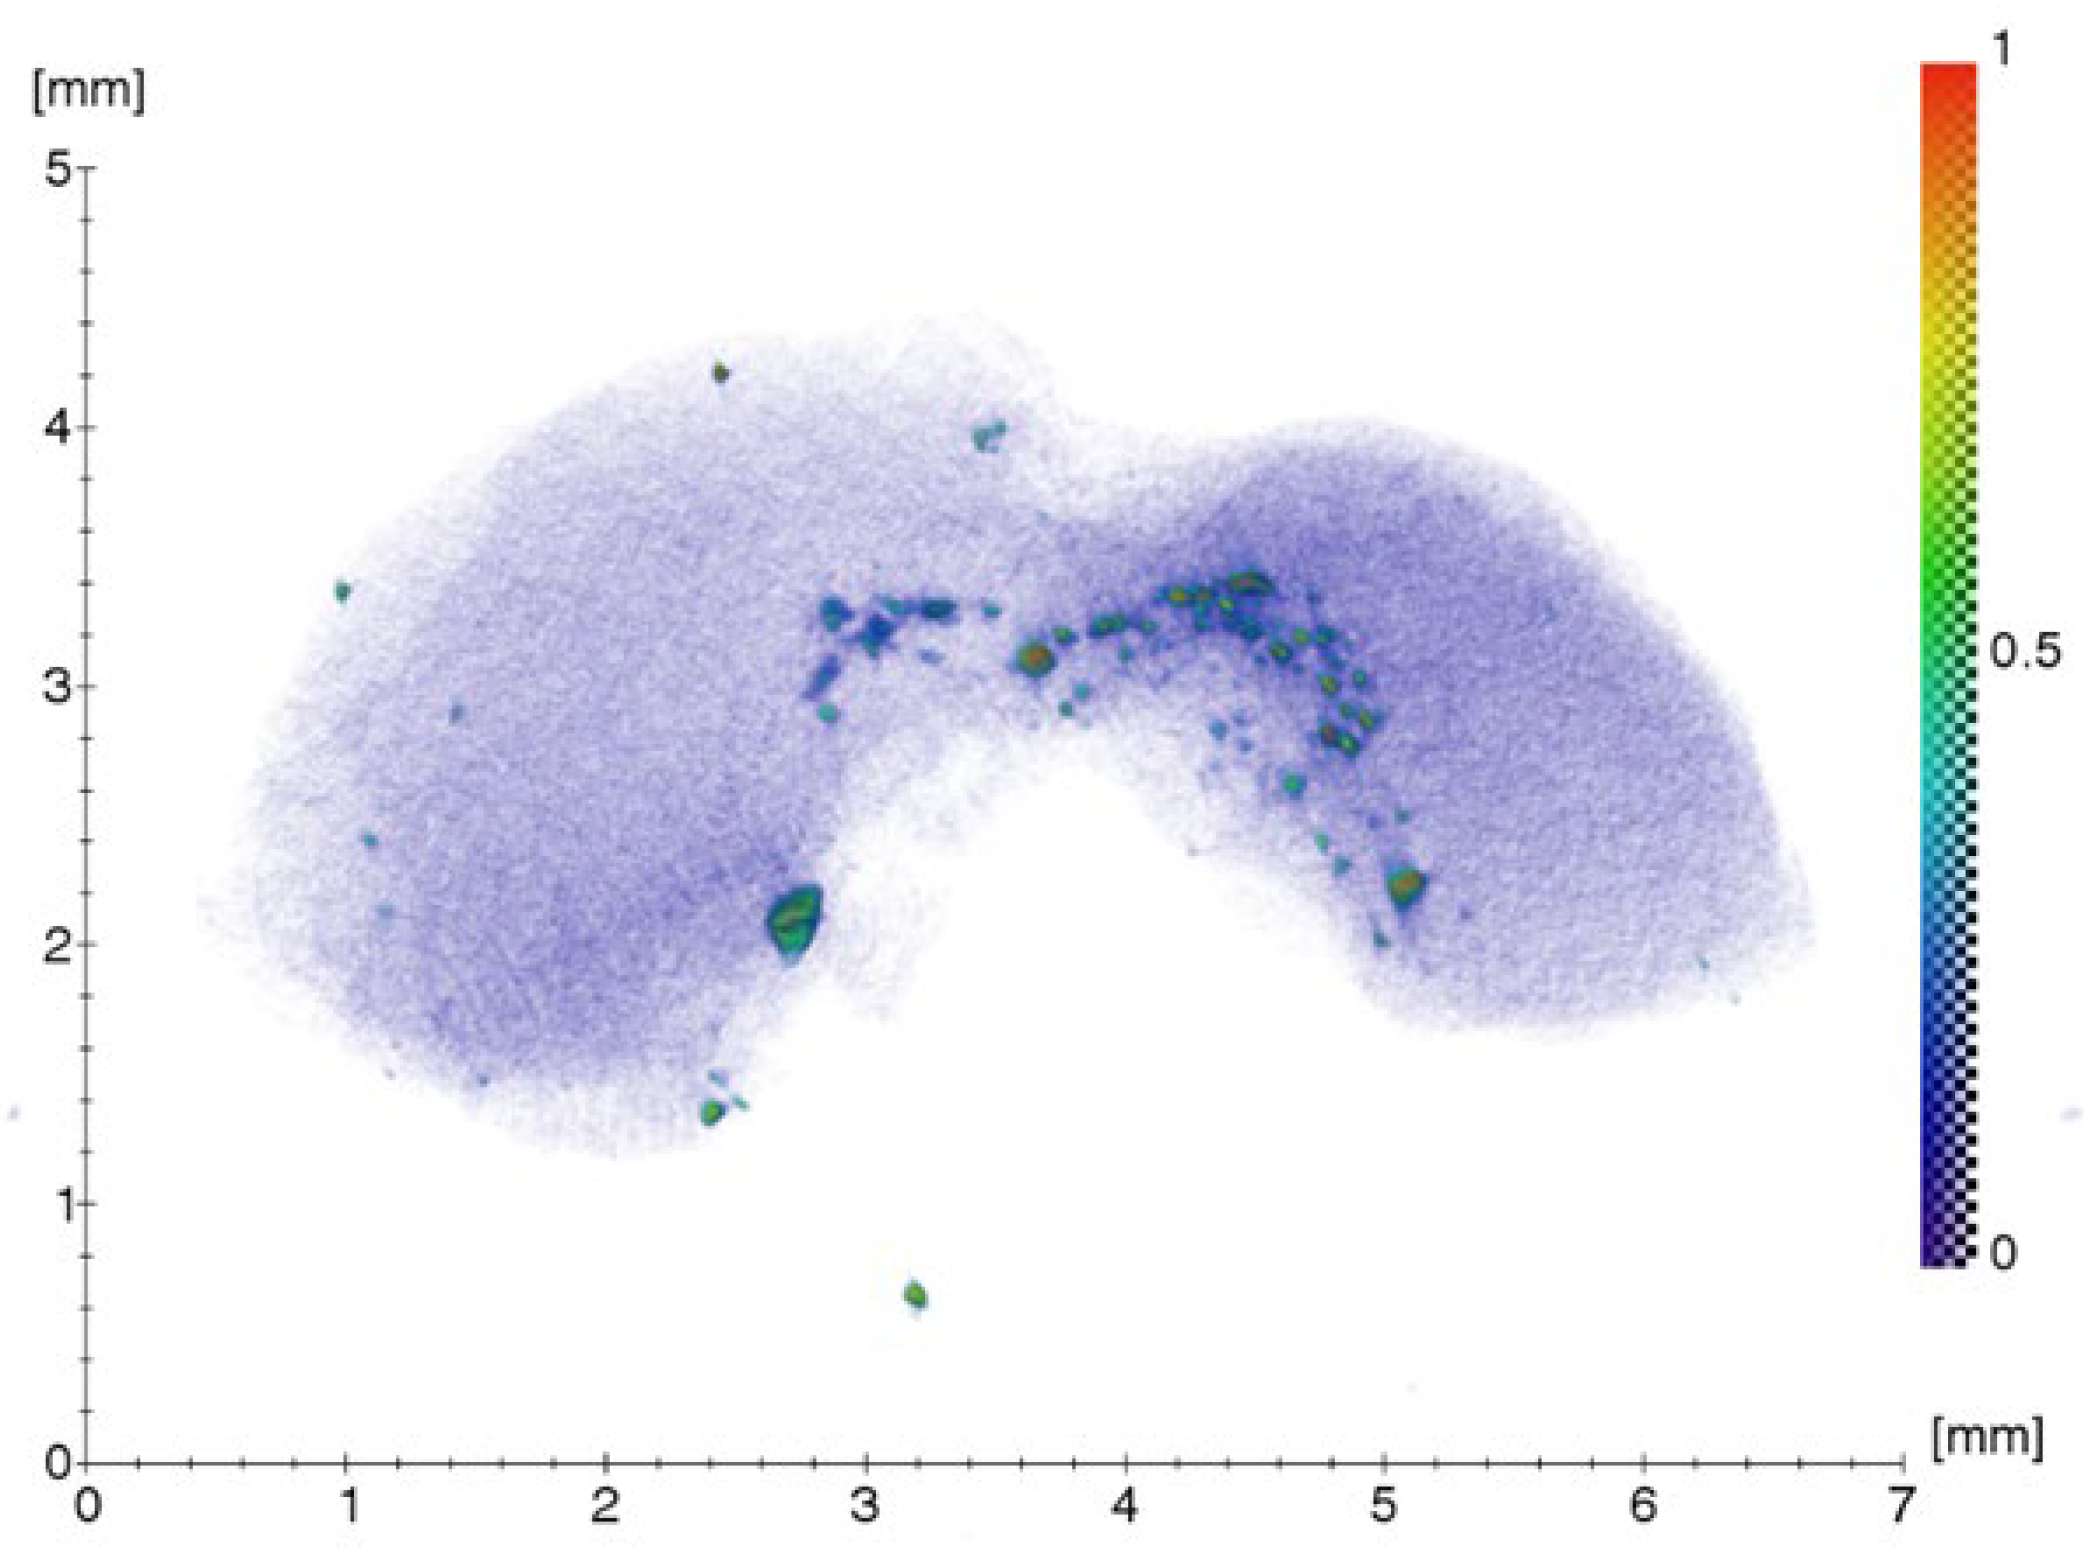

2.1.1. Results of X-ray and Electron Microscopic Studies

4.2. X-ray Microtomography (XMCT)

4.3. X-ray Fluorescence Analysis (XRF)